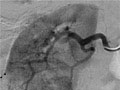

Una angiografía es una prueba radiográfica que utiliza un tinte y una cámara para obtener imágenes del flujo de sangre en una arteria o en una vena. La angiografía puede usarse para observar las arterias o las venas de la cabeza, los brazos, las piernas, el pecho, la espalda o el abdomen. Esta prueba se hace para detectar problemas en las arterias o en las venas.

Durante una angiografía, el médico le introducirá un tubo delgado y flexible en un vaso sanguíneo en la ingle o el brazo. Este tubo se llama catéter. El médico guía el tubo hasta el vaso sanguíneo que se va a examinar. A continuación se inyecta un tinte a través del tubo para hacer que la zona sea más fácil de ver. Se toman radiografías o imágenes de la zona.

Una vez que se haya colocado el catéter, se inyecta el material de contraste a través de él. Es posible que se le pida que inhale y contenga la respiración durante varios segundos. Se tomarán varias imágenes radiográficas, una tras otra. Estas estarán listas de inmediato para que su médico pueda observarlas. Debe permanecer muy quieto para que las imágenes sean nítidas. Es posible que se tomen más imágenes.